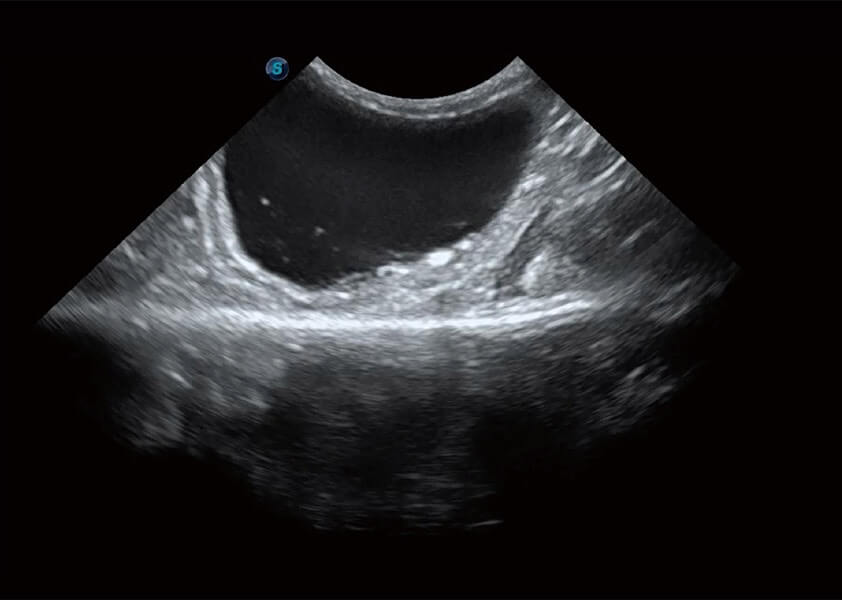

ProPet 60 作为一款高端台式动物超声设备,为动物医生的日常诊断提供了一系列贴合动物临床需求、解决临床实际问题的高级成像功能。凭借全系列高清探头,满足医生对腹部、心脏、生殖、浅表、肌骨等成像的所有需求,切实帮助您提升检查效率,提高诊断信心。

动物是人类最亲密的朋友和最值得信赖的伙伴。亚星官网也一直致力于探索动物专用的超声影像解决方案。 全新推出的ProPet系列,是亚星官网在动物超声影像智能化、专业化、精准化的一次跨越式革新。动物不能用言语来表述自己的不适,通过超声影像,ProPet系列搭建了动物医生与不同物种沟通的“桥梁”,为动物医生注入了“治愈之力”。